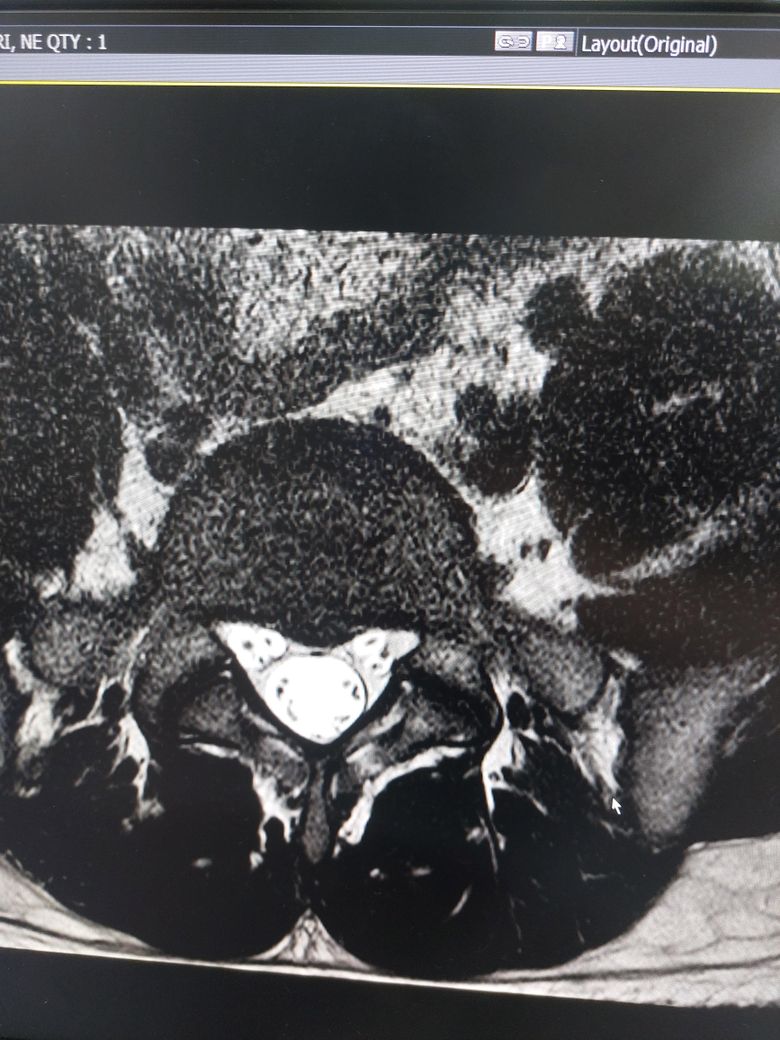

• 2번 째 사진

멸개월전부터 요추가 뻣뻣하고 시큰거리다가 최근에 좀 나아지긴 해도 만성적이라서 오늘 mri 찍고 허리디스크 진단받았습니다

(요추 맨 밑 천추 위 디스크)